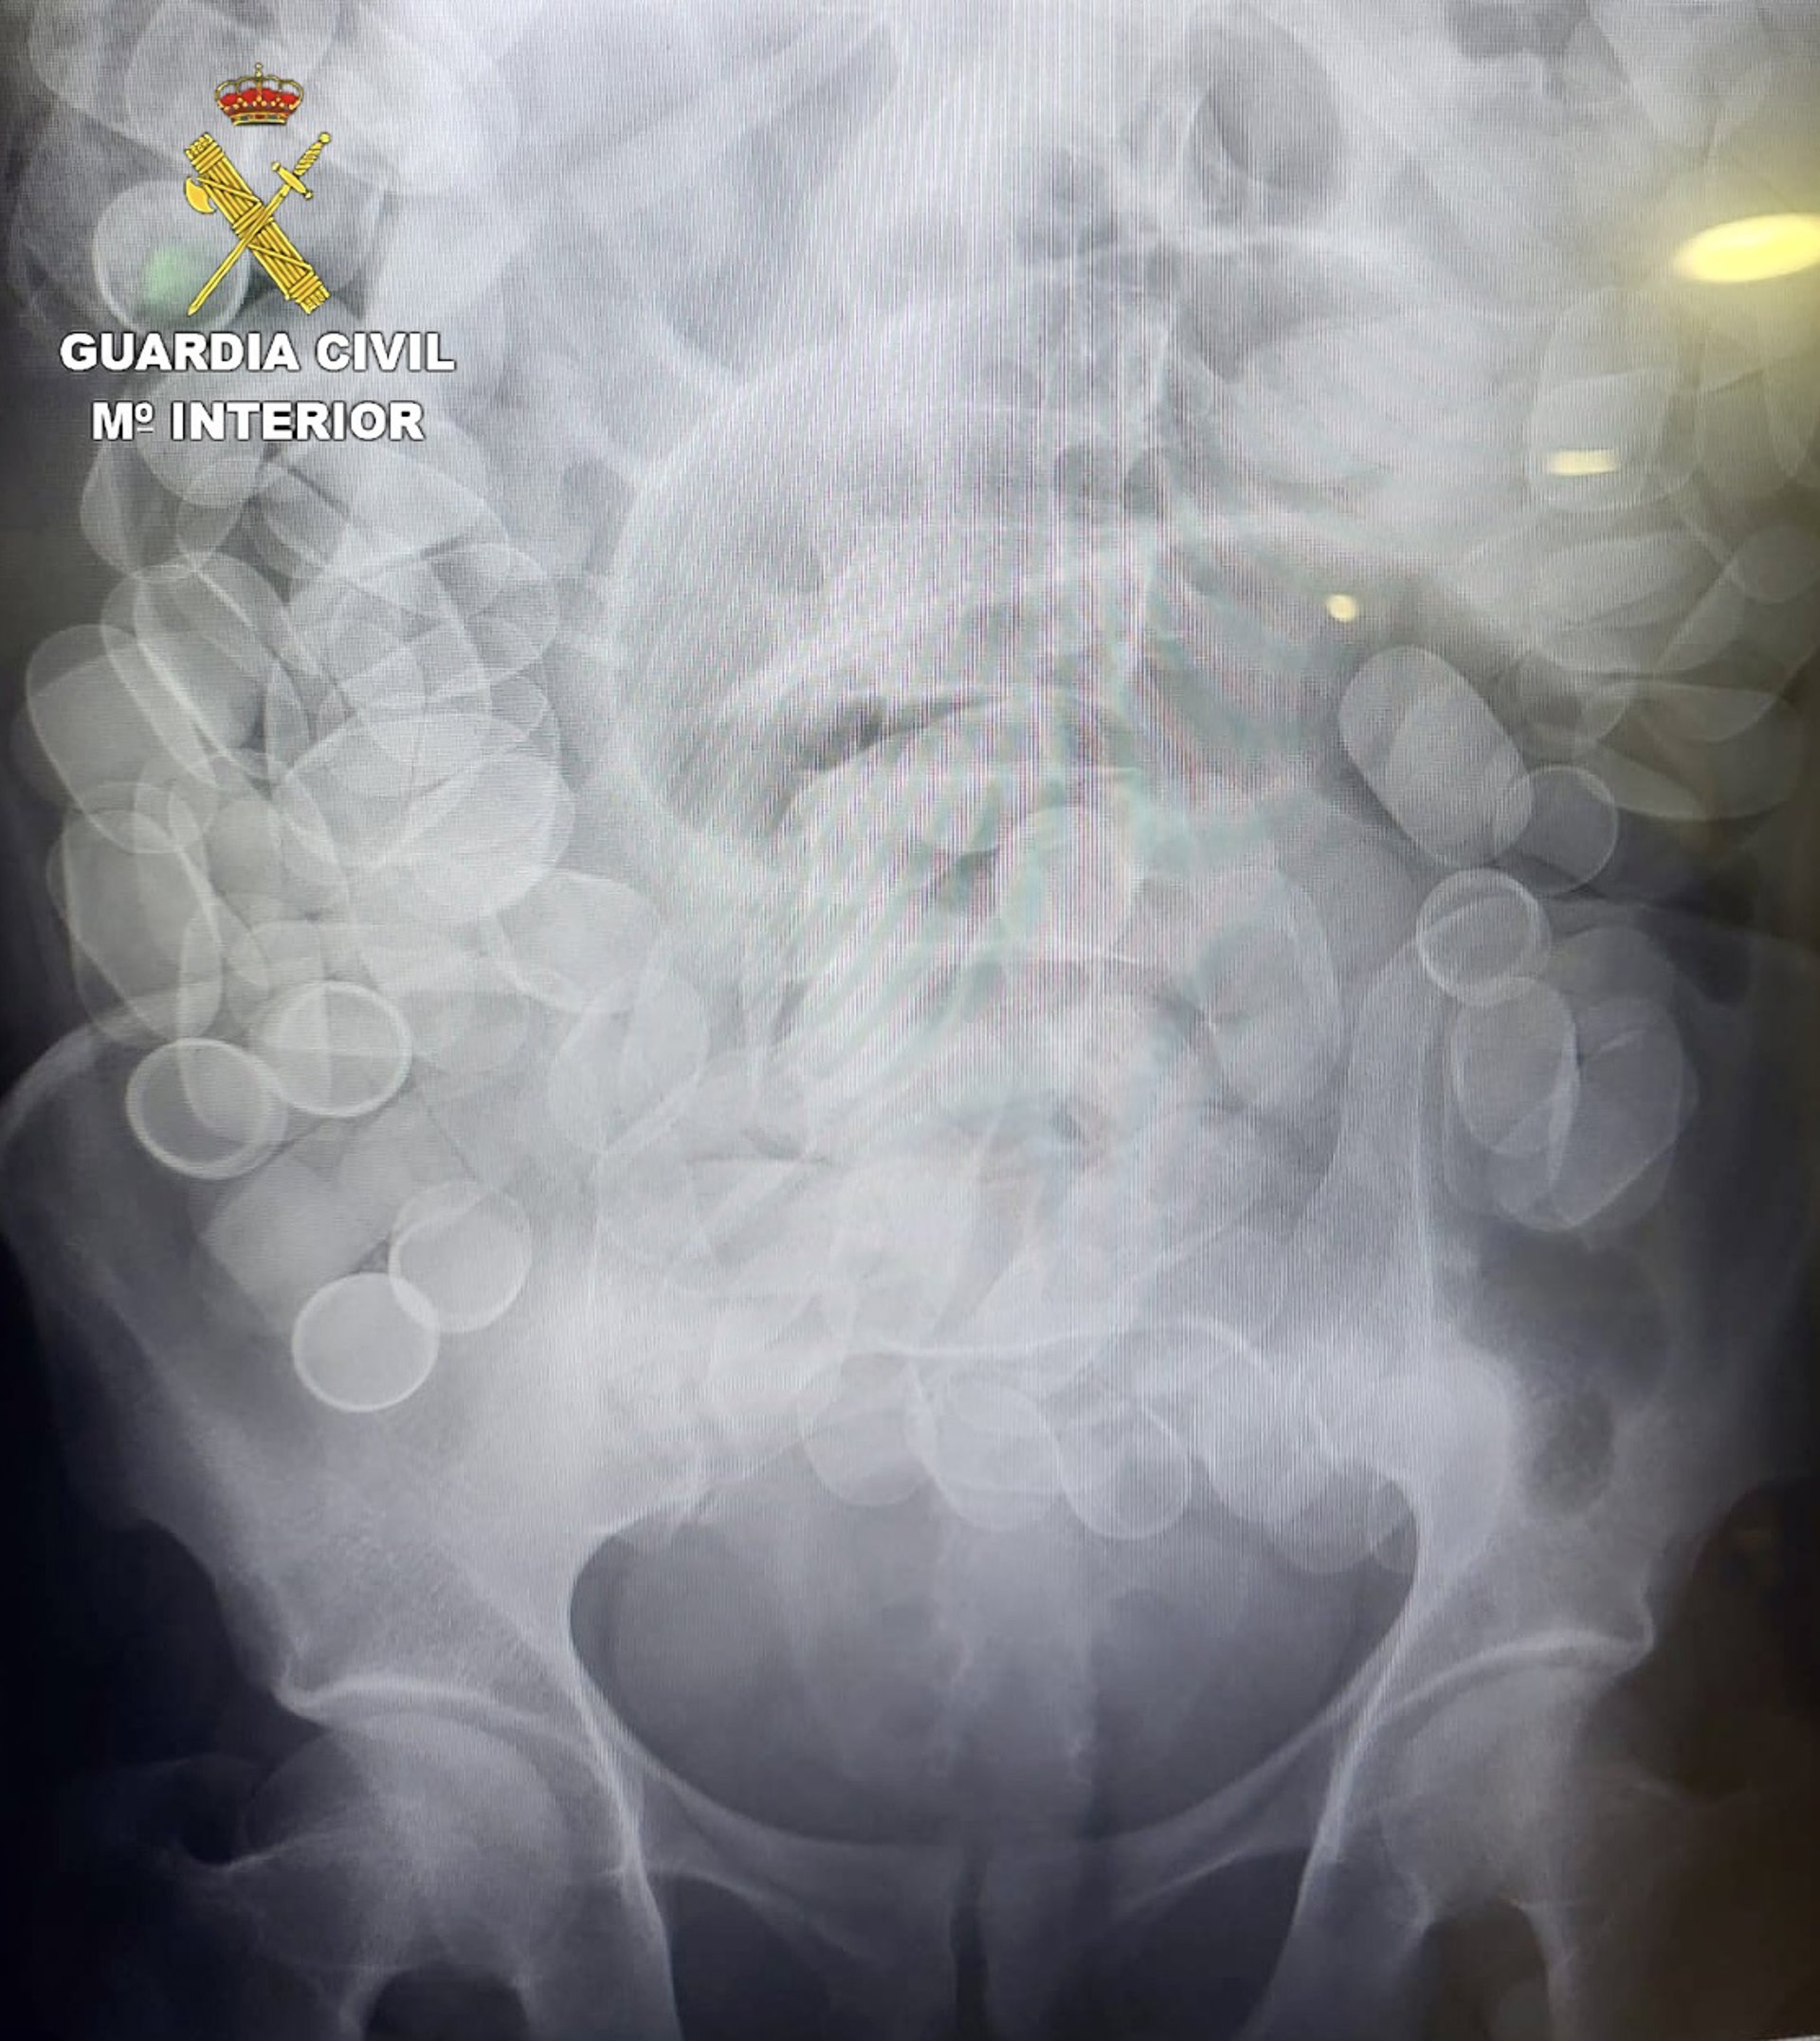

La prueba de rayos X practicada a un pasajero detenido en el Aeropuerto de El Prat de Barcelona que había ingerido 153 cilindros de cocaína

La prueba de rayos X practicada a un pasajero detenido en el Aeropuerto de El Prat de Barcelona que había ingerido 153 cilindros de cocaína - GUARDIA CIVIL

La Guardia Civil ha detenido en el Aeropuerto Josep Tarradellas-Barcelona El Prat a un pasajero que había ingerido 153 cilindros de cocaína con un peso total de un 1.480 gramos, según ha informado el instituto armado en un comunicado este miércoles.

Una vez detenido, los agentes comprobaron que su estado de salud no era bueno, por lo que fue trasladado rápidamente al Hospital de Bellvitge donde se confirmó la presencia de cuerpos extraños en su interior y tuvo que ser intervenido de urgencia porque algunos de los cilindros se habían roto.